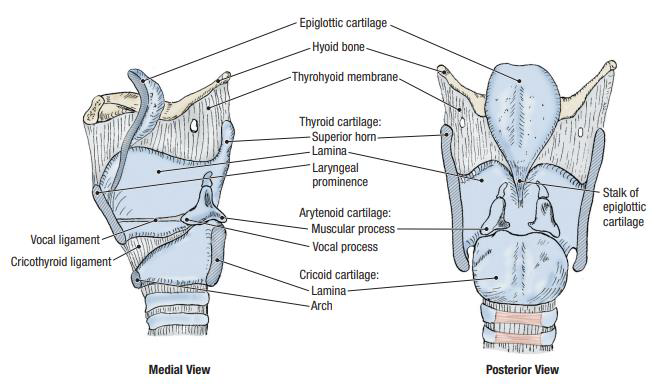

Larynx

Muscle

關閉 Epiglotticus

- Thyroepiglotticus m

- Aryepiglotticus

Vocal fold

Motor: Recurrent laryngeal n.

- Arytenoid m.

- Transverse fiber / Oblique fiber

- Vocal fold adduction

- Post. cricoarytenoid

- Vocal fold abduction

- Lateral cricoarytenoid m.

- Vocal fold adduction

- Thyroarytenoid m.

- Arytenoid cartilage 往前

Motor: External laryngeal n.

- Cricothyroid m.

假聲帶:Vestibular Fold

Artery

Nerve

- Sup. laryngeal n.

- Internal br.(Internal laryngeal n.)

- Sensor

- 穿過 Thyrohyoid ligament

- External br.

- Motor

- Internal br.(Internal laryngeal n.)

- Recurrent laryngeal n.

- Inf. laryngeal a.伴行

- 過Cricothyroid joint改叫Inf. laryngeal n.